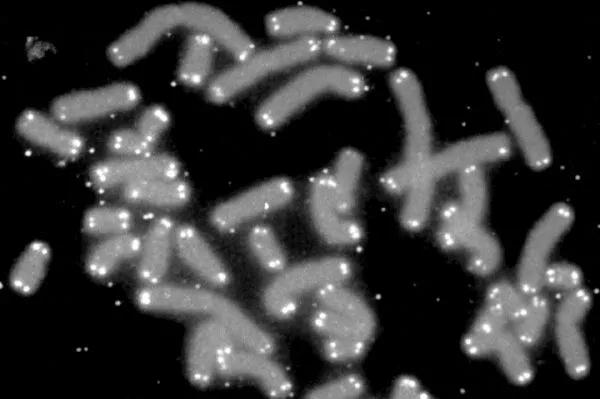

11月20日,據《每日郵報》報道,以色列科學(xué)家們取得了一項突破性研究。這是一項可以改變衰老狀態(tài)的生物學(xué)研究。在這項獨特的研究中,科學(xué)家們使用高壓氧療法,逆轉了生物衰老的兩個(gè)關(guān)鍵指標“端??s短”和“衰老細胞積聚”。

#01端粒長(cháng)度增加20%—38%;

#02細胞衰老減少11%—37%,具有顯著(zhù)的抗衰老作用。

端粒體: 它位于DNA的兩端,隨著(zhù)年齡的增長(cháng),它越來(lái)越短,這將會(huì )導致包括癌癥,阿爾茨海默氏癥和帕金森氏癥等的疾病。另一方面衰老細胞或者所謂的僵尸細胞也會(huì )在體內積聚,阻止細胞再生。直到最后由于它過(guò)短了,無(wú)法分裂了,生命就死亡了。

結果表明,該實(shí)驗使人體端粒再生長(cháng)了37%,而其衰老細胞減少了38%??茖W(xué)家說(shuō),這相當于他們25年前身體所處于的細胞水平。